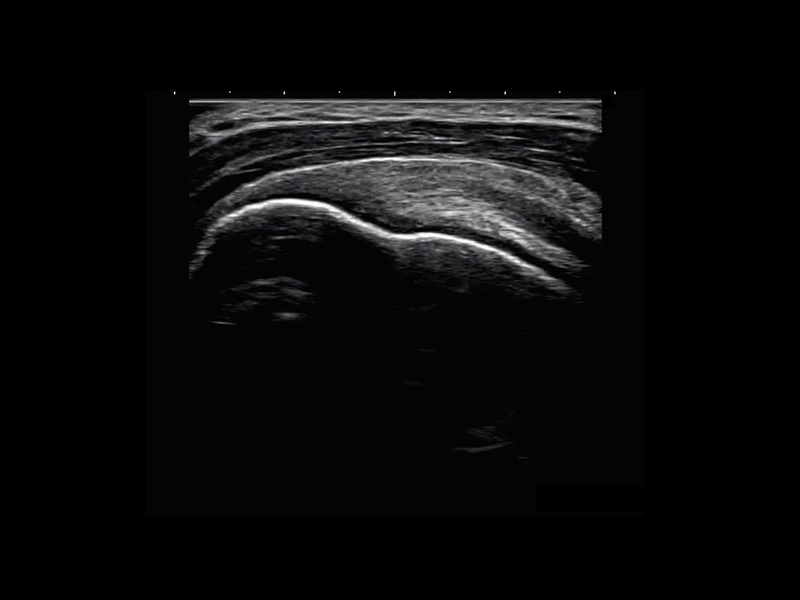

The system leverages an advanced imaging algorithm that achieves improved resolution of ultrasound images while maintaining optimum frame rates. The algorithm improves image quality of color and gray scale modes, delivering speckle reduction and applying a smoothing effect to reduce graininess in the image, helping clinicians make better informed diagnoses and facilitate accurate interventions.

The SONIMAGE® MX1 Platinum L18-4 Is a broad frequency linear probe that offers both near-field resolution and deep penetration for scanning both superficial and deep joints and structures. The advanced imaging algorithm dramatically enhances its resolution for more precise diagnosis. The HL18-4 hockey stick linear transducer is especially suited to MSK and pain management applications reaching difficult to access areas with its small footprint and maneuverability. Deliver exceptional patient care throughout the care path with the SONIMAGE MX1 Platinum S4-2 phased array transducer, especially in perioperative environments.

The MX1 Platinum System is a powerhouse in performance, leveraging an advanced imaging algorithm that achieves improved resolution and crystal-clear image quality, while maintaining frame rate. This unique powerful algorithm improves image quality of the color and grayscale modes, delivering speckle reduction and applying a smoothing effect to reduce graininess in the image, even on a compact monitor. The system’s sophisticated imaging empowers decision-making and facilitates accurate interventions, elevating patient care.